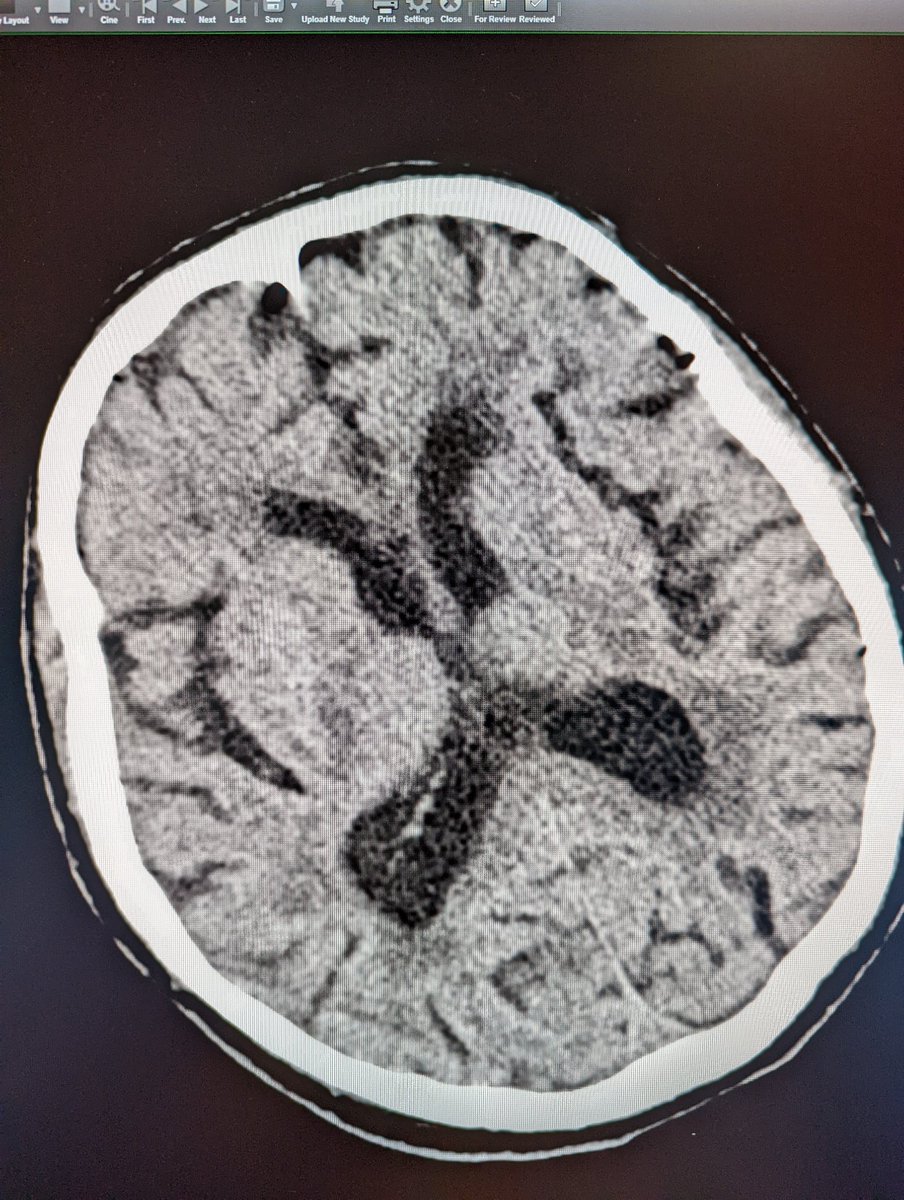

Neuro IR in Minneapolis. Proud product of UCSF. Husband to a Queen, father of 4 princesses. Die hard Buckeyes fan. Work hard, play harderr.